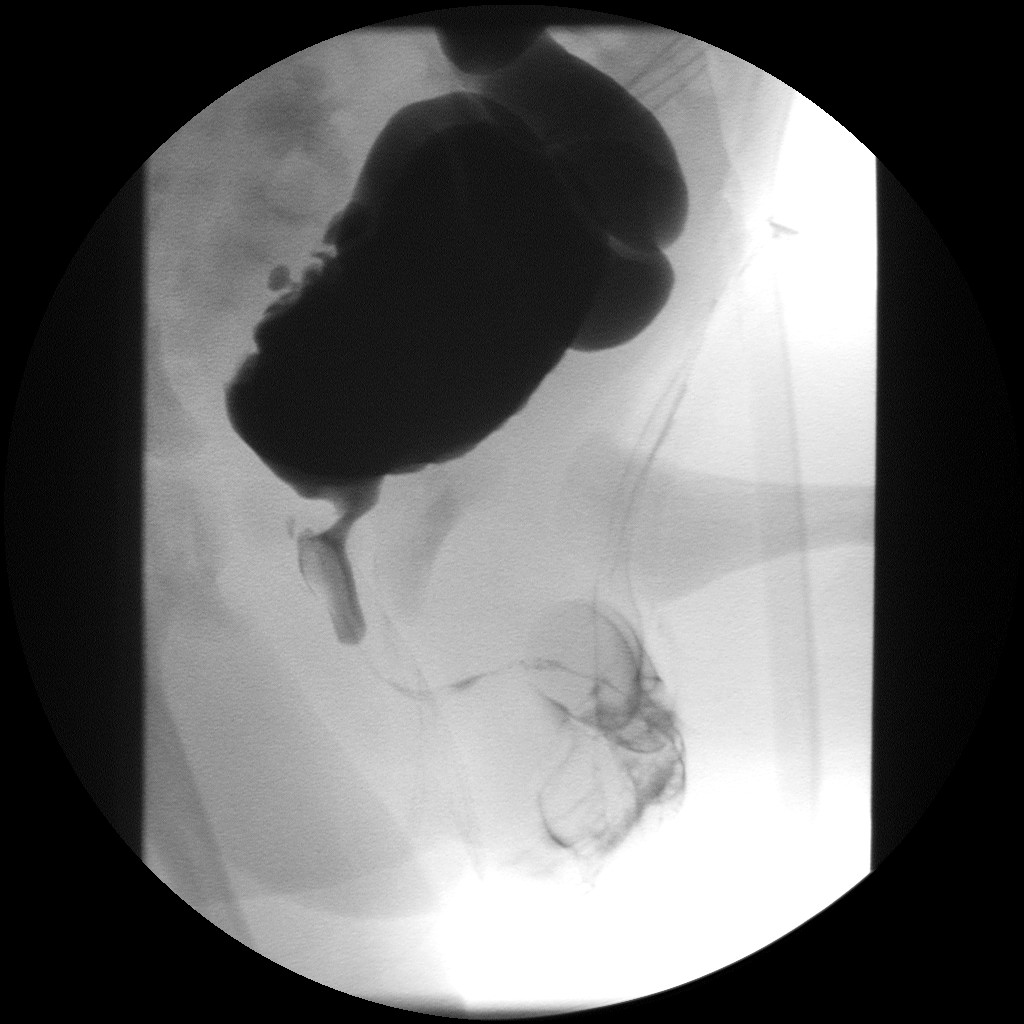

초음파 영상 검사는 방광의 모양, 배뇨 후 잔뇨량, 신장 크기, 두께 또는 요관 확장과 같은 신장 손상 증거에 대한 정보를 제공할 수 있다.[8] 초음파에서 방광 벽 비후는 수신증 및 결석과 같은 요로 이상이 발생할 위험이 높다는 것을 나타낸다.[9] 배뇨 방광요도조영술 검사는 조영제를 사용하여 방광이 가득 찼을 때와 배뇨 후의 영상을 얻으며, 이는 신경인성 방광과 일치하는 방광 모양의 변화를 보여줄 수 있다.[8]

요도 및 방광 확장을 동반한 요로 폐쇄를 나타내는 방광 요도 조영술